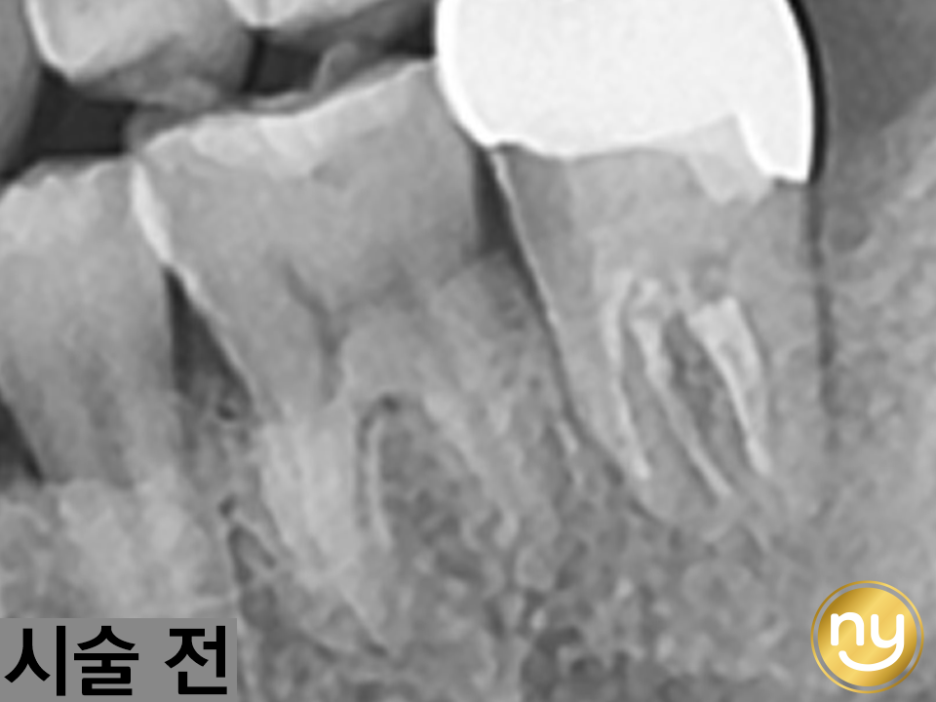

위 환자분은 충치가 많이 진행되어 신경치료한 치아를 사용하고 있었습니다.

하지만, 오랜 기간이 지나 치아 뿌리 끝에 염증이 생겨 발치를 권유받았는데요,

뿌리가 벌어져 있으면, 뿌리가 부러져 결국 재식술이 불가능해 발치를 할 수밖에 없습니다.

뿌리를 둘러싸고 있는 잇몸뼈가 없으면, 이물질 등이 침투해 치주 질환을 일으킬 수 있어

신경치료 후 염증 재식술을 실패할 수 있습니다.

따라서 CT 촬영을 통한 정밀한 진단 및 분석으로

뿌리 끝 염증을 세심히, 섬세히 관찰할 수 있어야 합니다.